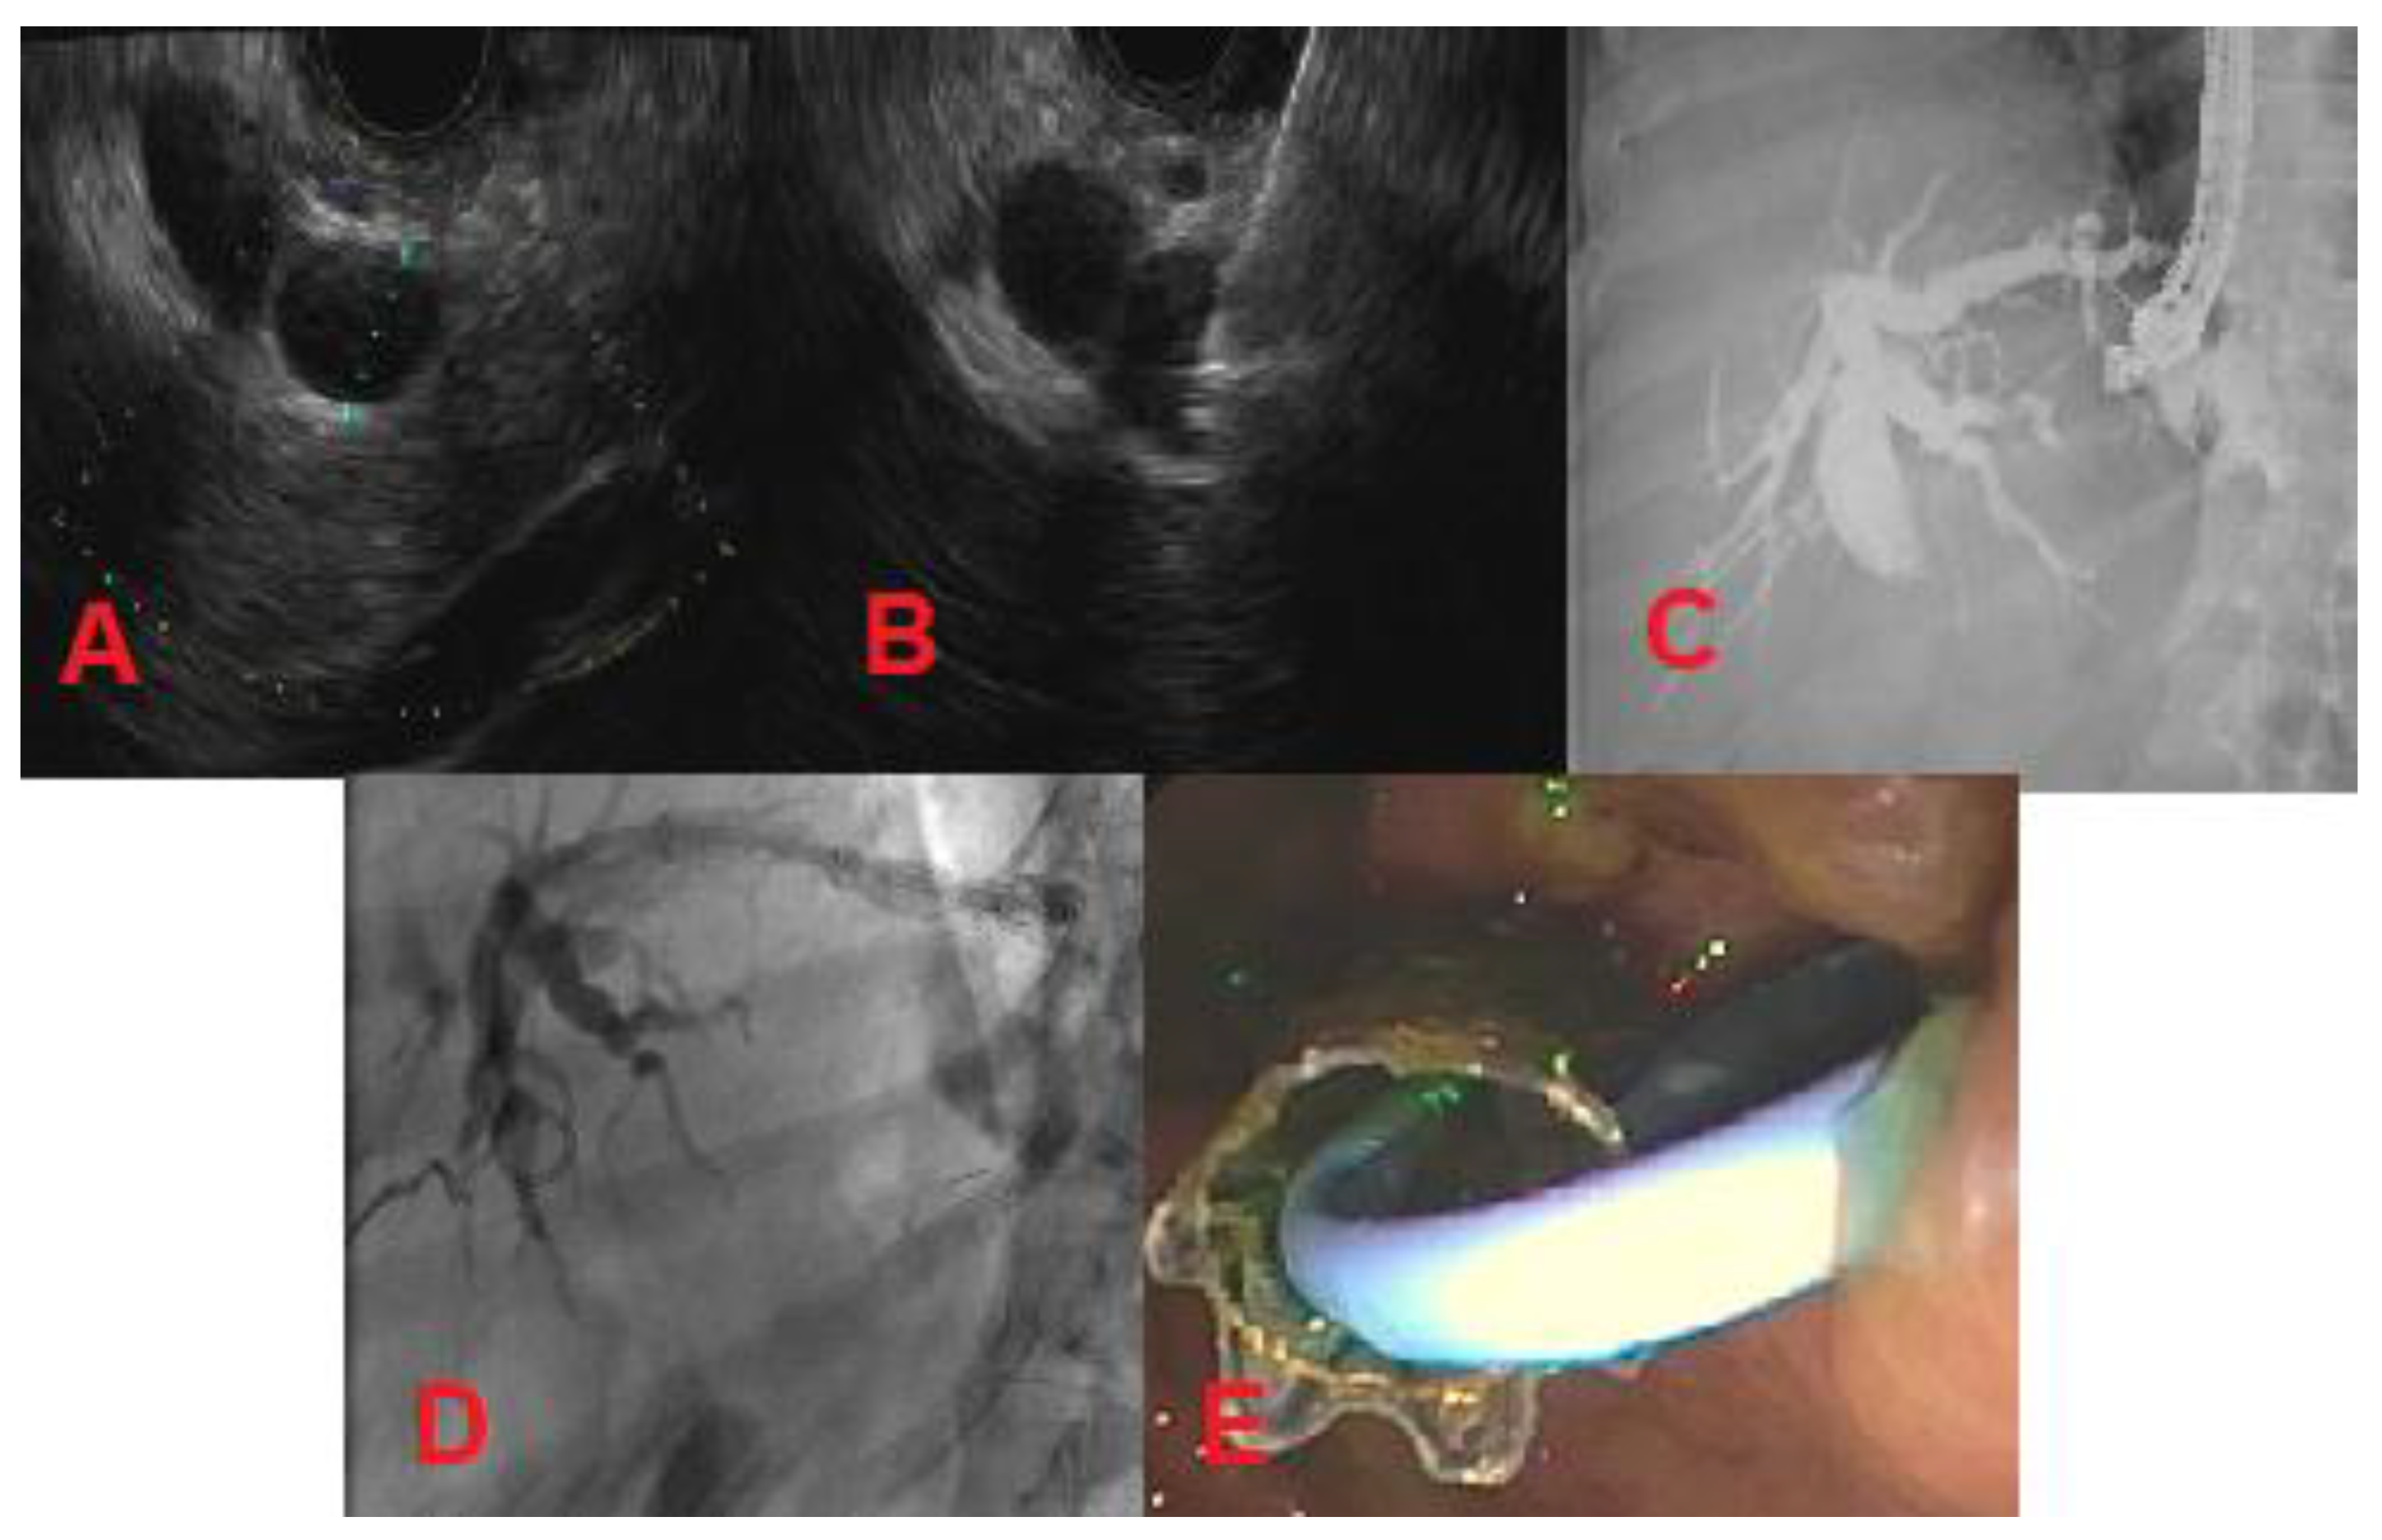

There are three types of EUS-BD: intrahepatic, extrahepatic, and EUS-guided rendezvous (EUS-RV). The intrahepatic and extrahepatic methods are used when the duodenal papilla is not accessible. Intrahepatic EUS-BD involves puncture of a dilated left intrahepatic biliary radicle under EUS guidance through the lesser curvature of the stomach followed by tract dilation and antegrade stent placement (transpapillary) or placement of a metal stent between the stomach and the liver (EUS-guided hepaticogastrostomy) (Figure 4) [32]. Extrahepatic EUS-BD can be achieved for distal biliary obstructions by draining the dilated common bile duct under EUS guidance directly into the duodenum (EUS-guided choledochoduodenostomy) or by draining the distended gall bladder into the gastric antrum or duodenum in cases where the cystic duct is patent [33]. While the EUS-guided hepaticogastrostomy and choledochoduodenostomy methods bypass the stricture by forming an alternate route, EUS-RV aims to cannulate the stricture to increase forward flow of the bile. The rendezvous process involves identifying a dilated hepatic duct on EUS and placing a guidewire through the hepatic duct, past the stricture into the duodenum. At this point, a duodenoscope is used to cannulate the lesion over the guidewire to perform a conventional ERCP [31]. As described, there are multiple methods of EUS-BD. Currently, there is no standardized approach to choose one technique over another. More research is needed to characterize the risks and benefits of each procedure and its efficacy with various types of MBS. However, EUS-BD in general will likely replace PTBD as the field advances.

Figure 4.

Metastatic pancreatic cancer (patient with history of Roux-en-Y gastric bypass surgery). (A) Dilated left intrahepatic biliary radicle; (B) Needle puncture of left intrahepatic biliary radicle using a 19-gauge needle; (C) Cholangiogram showing dilated intrahepatics, proximal and mid-common bile duct; (D,E) Left-sided hepaticogastrostomy.